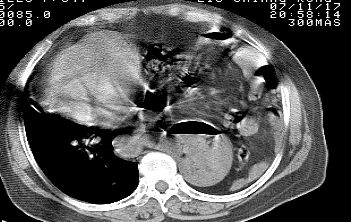

标题: CT10753:女, 64岁 隔疝 [打印本页]

标题: CT10753:女, 64岁 隔疝

女, 64岁 三十年前胸部外伤史, 间断胸闷,

典型左侧膈疝,疝出物为胃和大网膜,纵隔右移

同意左侧膈疝,不过,有过外伤史,左肺有受压征象,同时有胸膜增厚。